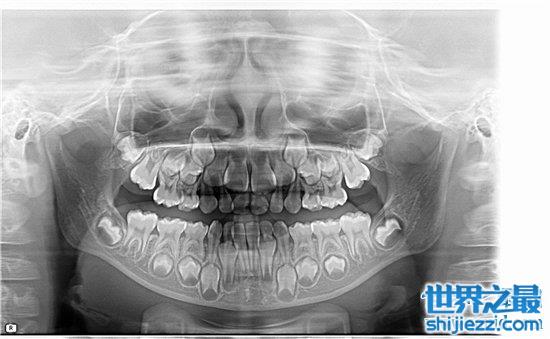

孩子是20颗牙齿,也就是说乳牙是20颗,而成年人是32颗。但是中国人有很多是没有最后四颗的,而这四颗是成年后长大的,也叫智齿。有的人不能长出,所以成年人的牙齿可以从28到32颗,但如果你拍摄X光片,你就可以看到它们。正常成年人只要没有被移除就会有32颗牙齿。

正常人通常有28-32颗牙齿,其中28颗是恒牙,4颗是智齿。当然,有些人没有智齿,有些人会有4颗智齿。这些都很正常,实际上有28颗牙齿起作用,当牙齿脱落一两个时,它不会影响整个身体的健康。然而,当牙齿逐渐脱落并且小于20时,它将影响身体的多个系统功能。

3、阻生牙

阻生牙是经常遇见的情况,特别是智齿很容易出现阻生牙的情况,阻生牙会导致邻牙的牙根吸收、邻牙蛀牙、邻牙牙周炎、牙列拥挤和冠周炎等,给口腔的健康造成极为不利的影响,因此需要尽早进行拔除。

5、多生牙

有些宝宝会出现牙齿中间出现多余的牙齿萌出,这样的多余牙会造成牙齿拥挤,因此,需要尽早进行拔除。